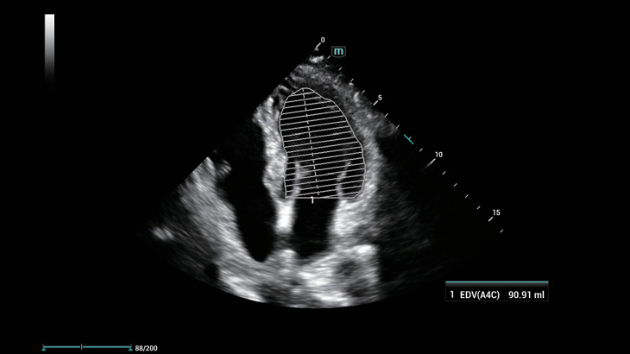

ZST+ ??? ???? ?? ???

ZST+ ???? ???? ??? ???? ??? ?????. ??? ???? ?? ? ???? ?? ??? ?? ??? ?????. ??? ??? ? ?? ??? ??? ???? ?????? ??? ???? ???? ??? ?? ?? ?? ?? ???? ?? ??? ?? ??? ?????.